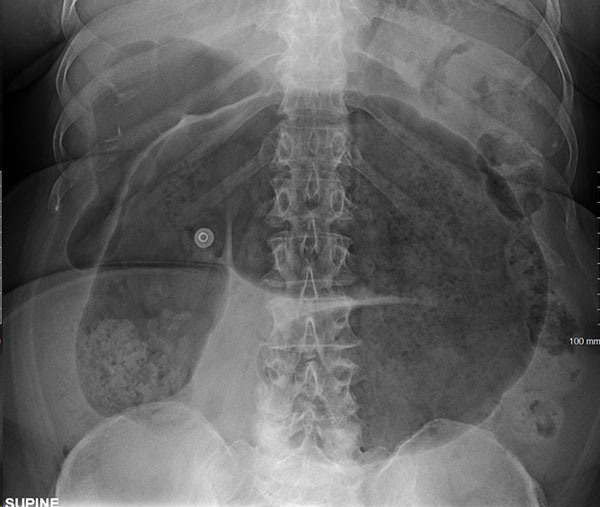

Patients with volvulus may present with acute generalized abdominal pain and distention. There may be reduced bowel sounds because of cessation of normal peristalsis.152 The coffee bean and bird beak signs on plain films have been described for both cecal and sigmoid volvulus, respectively. The inverted “U” sign extending into the right upper quadrant is specific to sigmoid volvulus.152 Plain film studies may demonstrate classic findings of sigmoid volvulus in about two-thirds of all cases.153 CT of the abdomen and pelvis with IV contrast is the preferred imaging study. CT signs of volvulus include absence of rectal gas (90%), inverted “U” sign (86%), coffee bean sign (76%), disproportionate sigmoid enlargement (76%), and northern exposure sign (57%).154 (See Figure 2.)

Figure 2. Cecal Volvulus |

Source: James Heilman, MD, under the Creative Commons Attribution-Share Alike 4.0 International license: https://creativecommons.org/licenses/by-sa/4.0/deed.en |